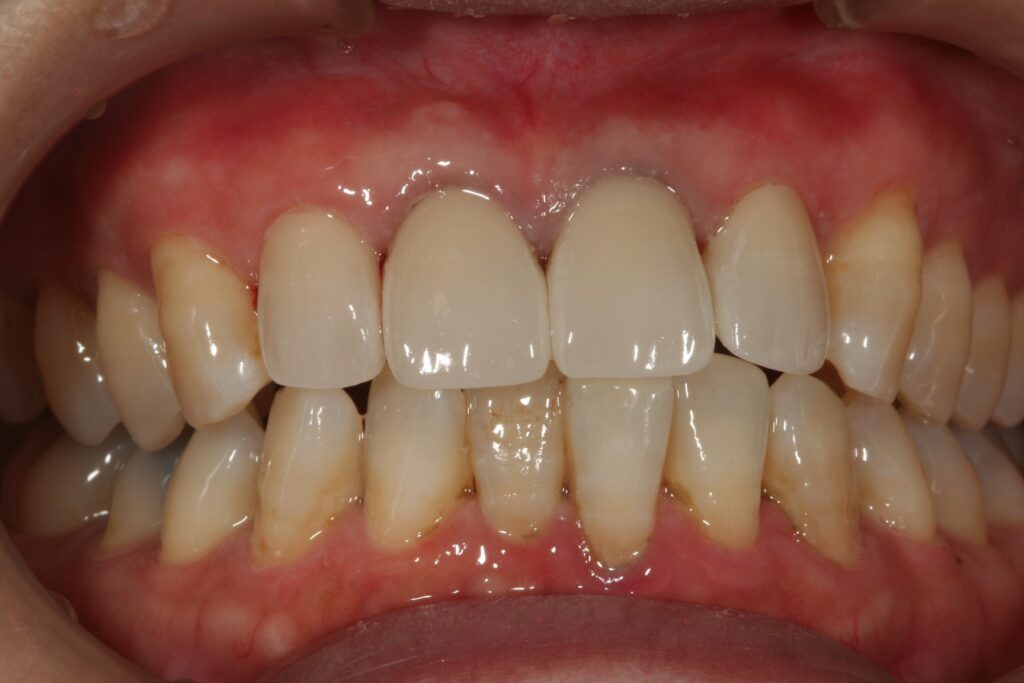

審美治療 2015.09.26 症例紹介 10年以上前から前歯の見かけが気になっておられました。1回目:カウンセリング2回目:治療、型取り、仮の歯3回目:取り付けて終了 でした。 症例紹介 都市伝説、、、、、前の記事 歯石とは?次の記事